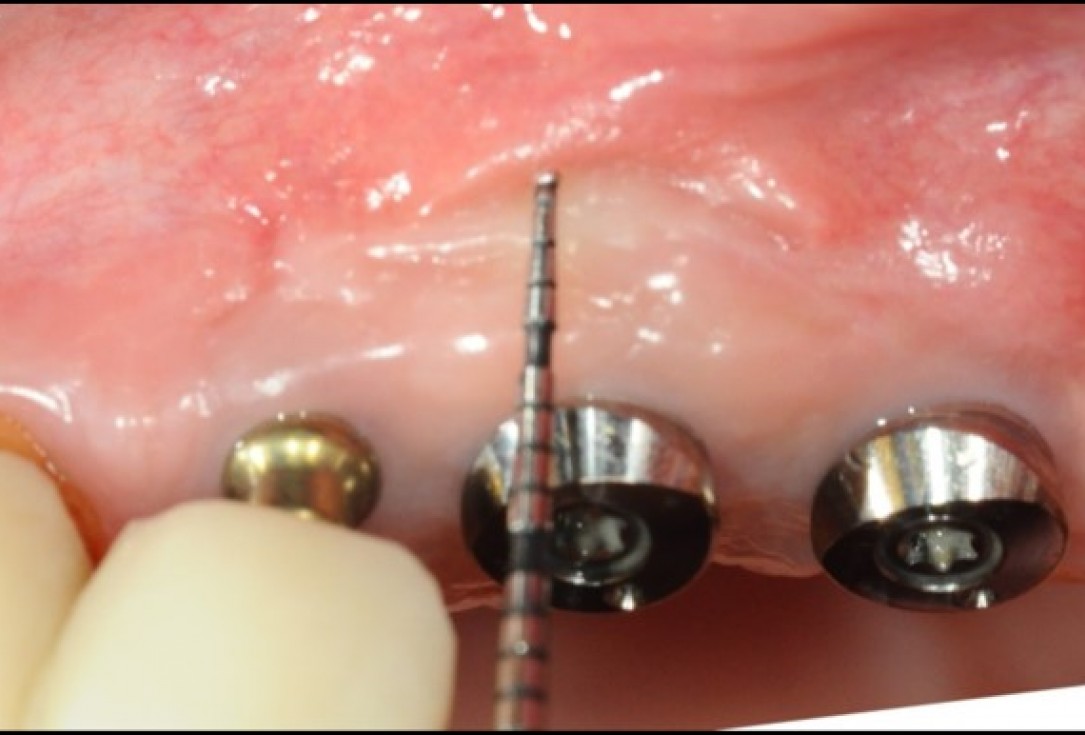

8/9 - Sufficient keratinized mucosa and deep vestibuleWidening of the peri-implant keratinized mucosa in the upper jaw with mucoderm®- Dr. A. Horváth